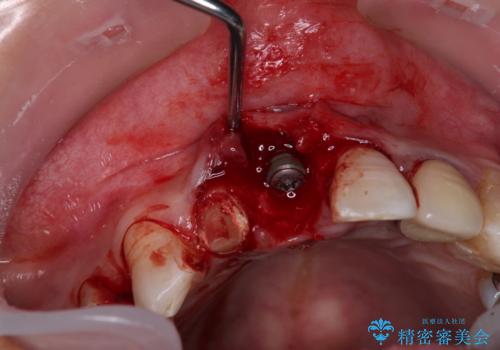

事前に仮歯を用意し、中切歯を抜歯した後に側切歯を土台とした仮歯を装着することで、審美的な問題が起こらないようにすることとしました。

側切歯は根管治療を行い、中切歯部は骨の再生を待ってインプラントを埋入し、その後2本合わせてオールセラミッククラウンにて補綴治療を行うこととしました。

現在では、抜歯時にインプラントを埋入し。同時に仮歯を装着する「抜歯即時埋入・即時荷重インプラント」での取り扱いとなりますが、治療当時は未導入であったため、従来の複数回の外科処置を行う術式で治療を行いました。そのため、歯肉の位置が上方に移動した位置での仕上がりとなりました。